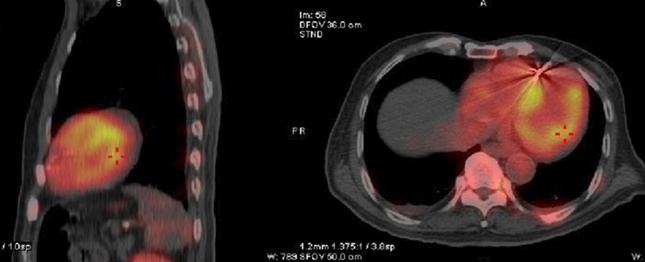

▲核医学科心肌核素pyp显像结果,是检测ATTR-CM的重要手段

“随着诊断技术的不断进步,有些曾经被认为是罕见病的疾病,很可能只是缺乏早期精准诊断方式。这些年,我们临床发现不少曾被诊断为缺血性心肌病、心衰、心肌肥厚等疾病的患者,其实可能背后都是因其他疾病引起的。如果不找到确切的病因,肯定会影响预后。”心内科主任郭晓纲主任医师说,2019年,浙大一院核医学科在省内率先开展心脏99mTc标记的焦磷酸(PYP)核素显像。多项临床研究表明,PYP核素检测诊断ATTR-CM的精准度达到90%以上,这是诊断ATTR-CM的非常有力手段。多项临床研究表明,PYP核素检测诊断ATTR-CM的精准度达到90%以上,这是诊断ATTR-CM的非常有力手段。